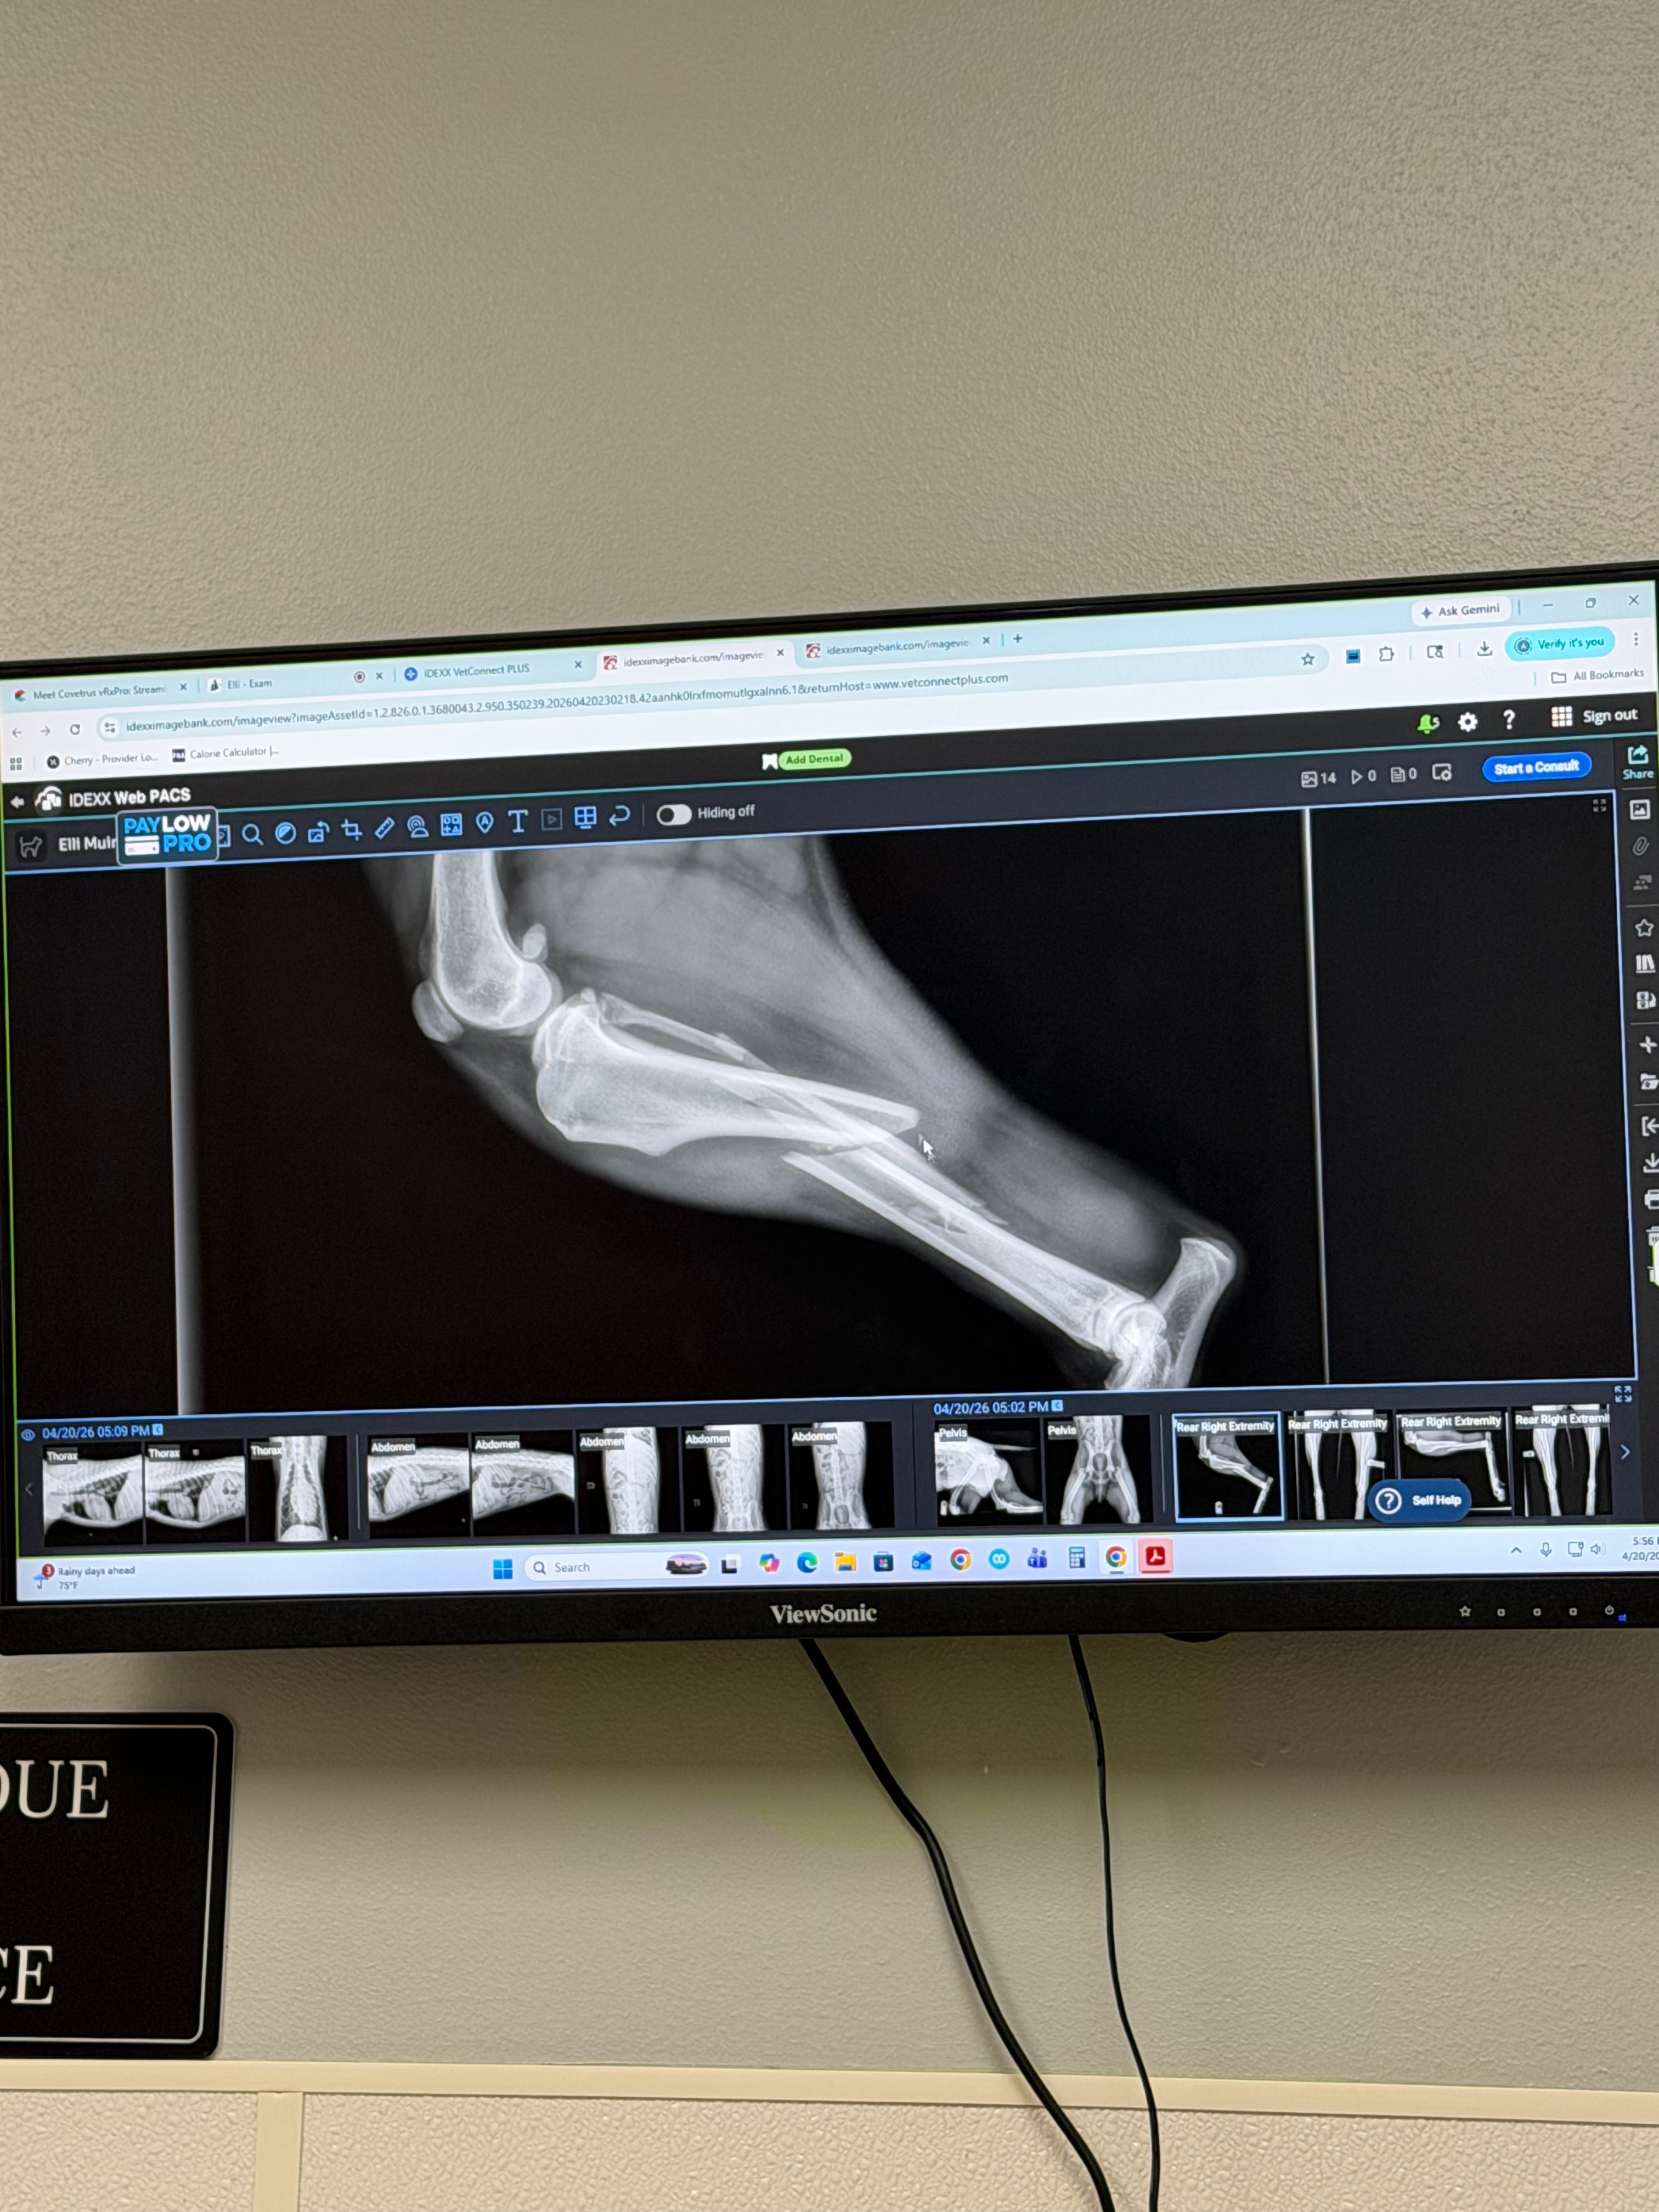

She survived, but her leg is severely injured. She can’t put any weight on it, and it’s visibly broken and just hanging. It’s been heartbreaking to see her in so much pain.

We got her fully examined today, and to keep her leg and do the fracture repair, the surgery is estimated to cost $4,400.